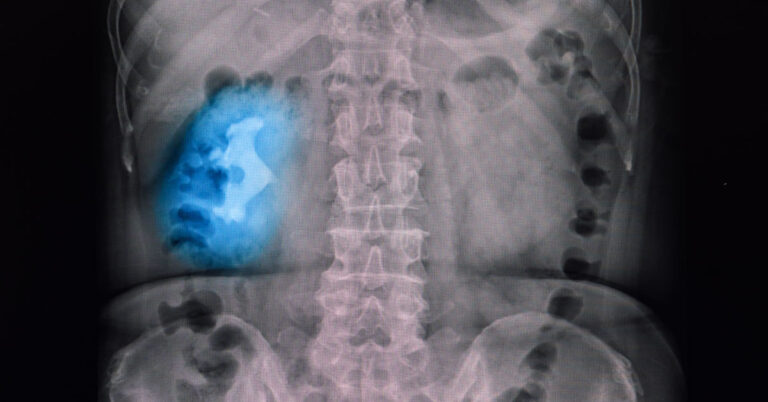

This site contains product affiliate links. We may receive a commission if you make a purchase after clicking on one of these links Staghorn stones are large, branching kidney stones that can wholly or partially fill the renal pelvis and calyces (Healy & Ogan, 2007). They are typically found on one side of the body and...